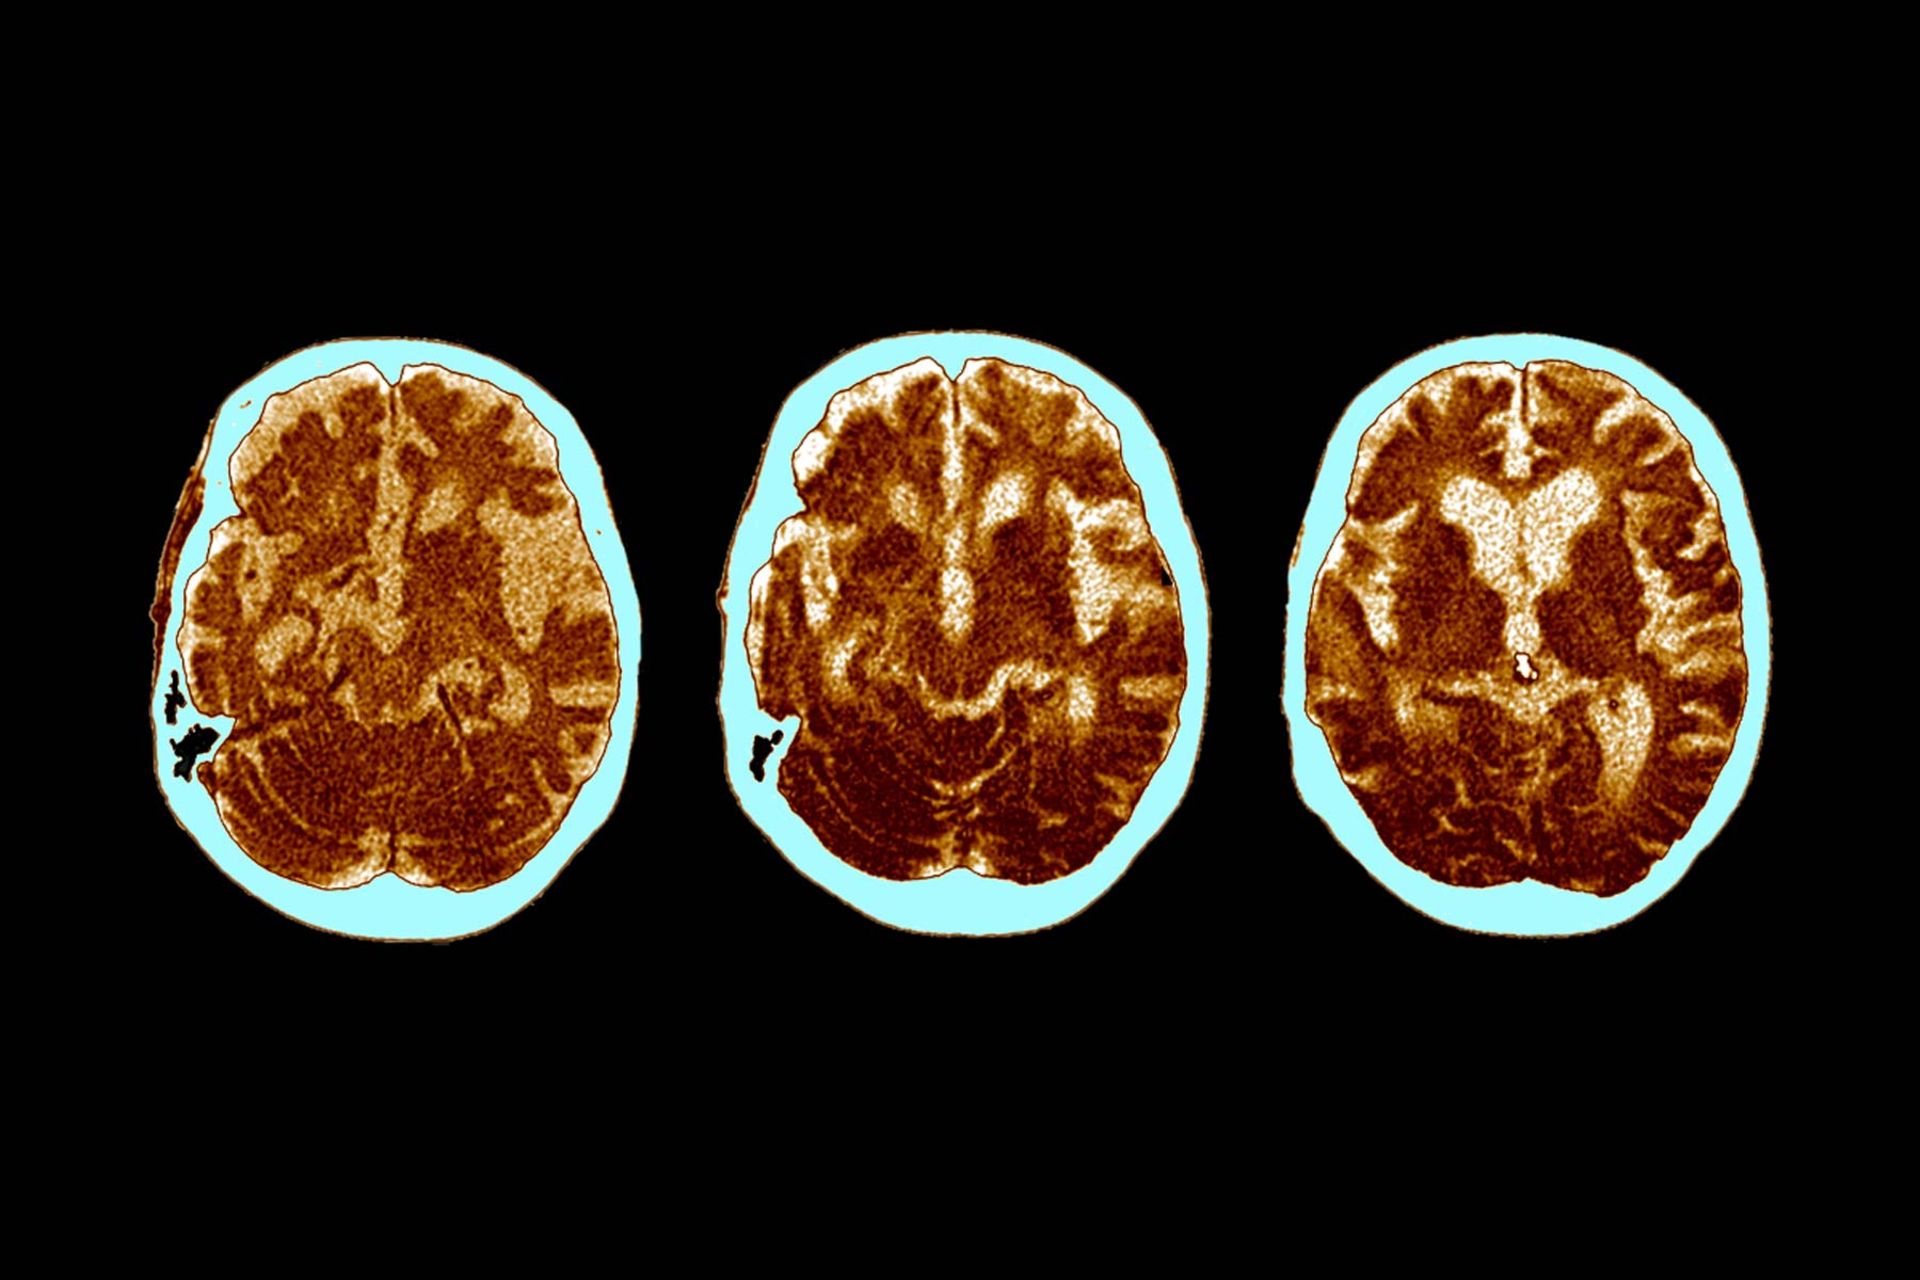

CT مغز بیماری با آلزایمر

برخی افراد به طرز عجیبی در برابر بیماری آلزایمر مقاوم هستند. چه چیزی باعث تفاوت آن‌ها با دیگر افراد می‌شود؟